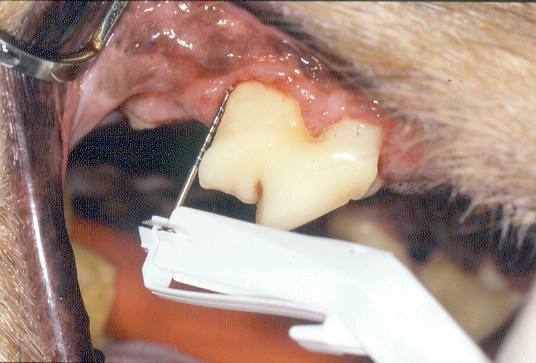

Gingival Recession

It is possible for the inflamed gingiva to recede apically. Once the microbes of periodontal disease come within 0.5mm of the bone crest it also recedes and all the tissues move apically in their normal relationship without forming a pocket.

The net result is exposure of the cemento-enamel junction and root surface but typically, no increase in sulcar depth and no pocket.